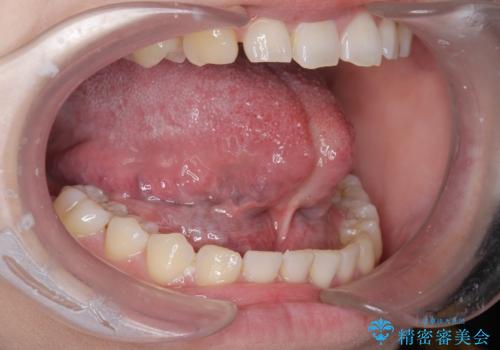

- 舌小帯を切りたいとの事で来院。

麻酔を行い、舌小帯切除術を行いました。

舌の可動域が広がりました。